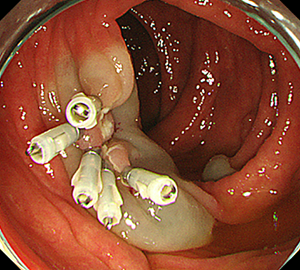

内視鏡的粘膜切除術(EMR)

外来にて切除することの出来ない、比較的大きめの大腸ポリープや平坦な病変などの切除の際に行います。

![]() |

|

| 1:ポリープを見つけ、NBI併用拡大観察をした後、 | 2:ポリープ直下の粘膜下層に局注液を注入し盛り上げます。 | |

| 3:ポリープをスネアに通し、周囲の正常粘膜を入れて病変を絞扼 | 4:電気を流してして切除します。 | |

||

| 5:切除面をクリップで縫合閉鎖し、回収した検体の病理検査に提出します |